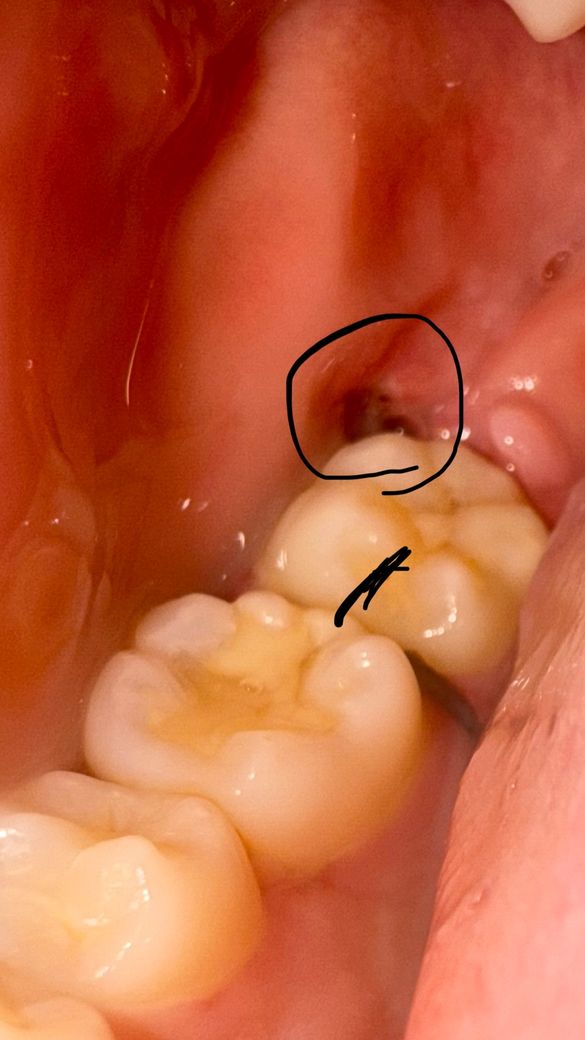

사랑니랑 과잉치를 뽑았는데 이거 염증일까요?

저번주 토요일날 발치했습니다 근데 오늘 보니 발치한 부분에 저런게 생겼는데 혹시 염증일까요? 염증이 생기면 혹시 입 옆쪽의 턱이 아픈가요? 입 옆쪽 턱부분이 아픈데 괜찮은건가요? ㅠㅠ

• 1번 째 사진

사진만으로는 판별하기 어렵지만 특별히 염증 반응이 나타나는 것 같지는 않습니다. 괜찮습니다.

정상적으로 아물고 있습니다. 원래 사랑니나 다른 치아라도 뽑은 자리에는 처음에 구멍이 생기지만 시간이 지나면 점점 차 올라옵니다.

염증은 아니고 아직 잇몸이 다 아물지 않아서 그런거니 너무 걱정은 안하셔도 될것같습니다.

발치 부위 염증이 생긴 것은 맞는 것 같은데 턱 주위 통증과는 별개로 보셔야 할 것 같습니다. 일단은 발치 후 처방받은 약 잘 복용하시고 발치 부위 부종가라앉았다면 턱부위는 냉찜질 말고 온찜질해주세요.